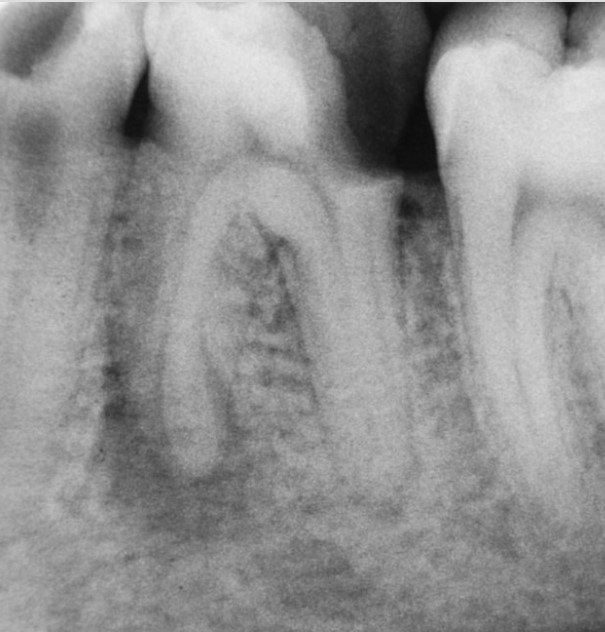

Die stille, schleichende und daher oft chronische, häufig nicht bemerkte, Erkrankung meint die Entzündung des Zahnfleisches (= Gingivitis) und, schwerer wiegend, die Zerstörung des Zahnhalteapparates (= Parodontose). Das kann bis zum Zahnverlust führen. Insbesondere aber sind die schleichenden systemischen Folgen im Organismus (siehe oben) problematisch, da eine unzureichende Mundhygiene über die Zeit schwerwiegende Erkrankungen und vorzeitigen Tod nach sich ziehen kann. Das geschieht, wenn von den in der Mundhöhle vorkommenden Bakterien für uns giftige Stoffwechselprodukte oder gar Bakterien in die Blutbahn gelangen, die dann auch andernorts im Körper zu schwelenden Entzündungen führen.